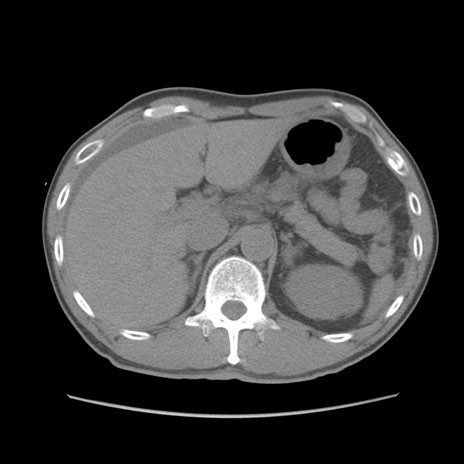

症例56 CT(横断像)

脂肪ウインドウ